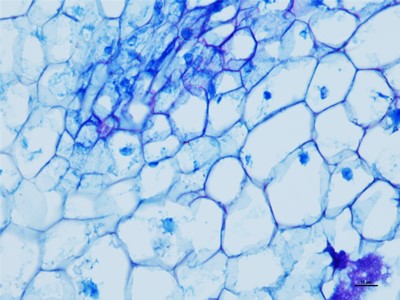

我们要在显微镜底下观察细胞的时候,就得把组织和细胞以及需要观察的东西切片,这些就得控制在厚度大概在1-10微米,这个厚度是最好观察物质的,如果没有在这个厚度之间的切片基本在观察就没有什么颜色。下面陕西依科生物技术有限公司针为大家介绍HE染色的具体操作步骤。

HE染色是基本病理的染色技术,HE染色是病理医生可以正确判断的唯一准则,首先在做实验的时候要准备乙醇、冰丙酮、苏木精染液、伊红染液、二甲苯、黑龙江中性树胶、培养瓶、培养皿、盖玻片、载玻片、显微镜等一些器材。首先将黑龙江石蜡切片脱蜡然后在将切片放进二甲苯无水乙醇,酒精,然后切片在放进伊红染色液中染色,然后就是将切片放入酒精和无水乙醇、二苯甲,脱水然后将切片拿出晾干,然后在封片。然后在用显微镜观察,图像采集。我们在做HE染色的实验时要注意以下细节,首先是脱蜡时要保持干净,已经苏木精染色的时间。以上就是HE染色的操作流程。